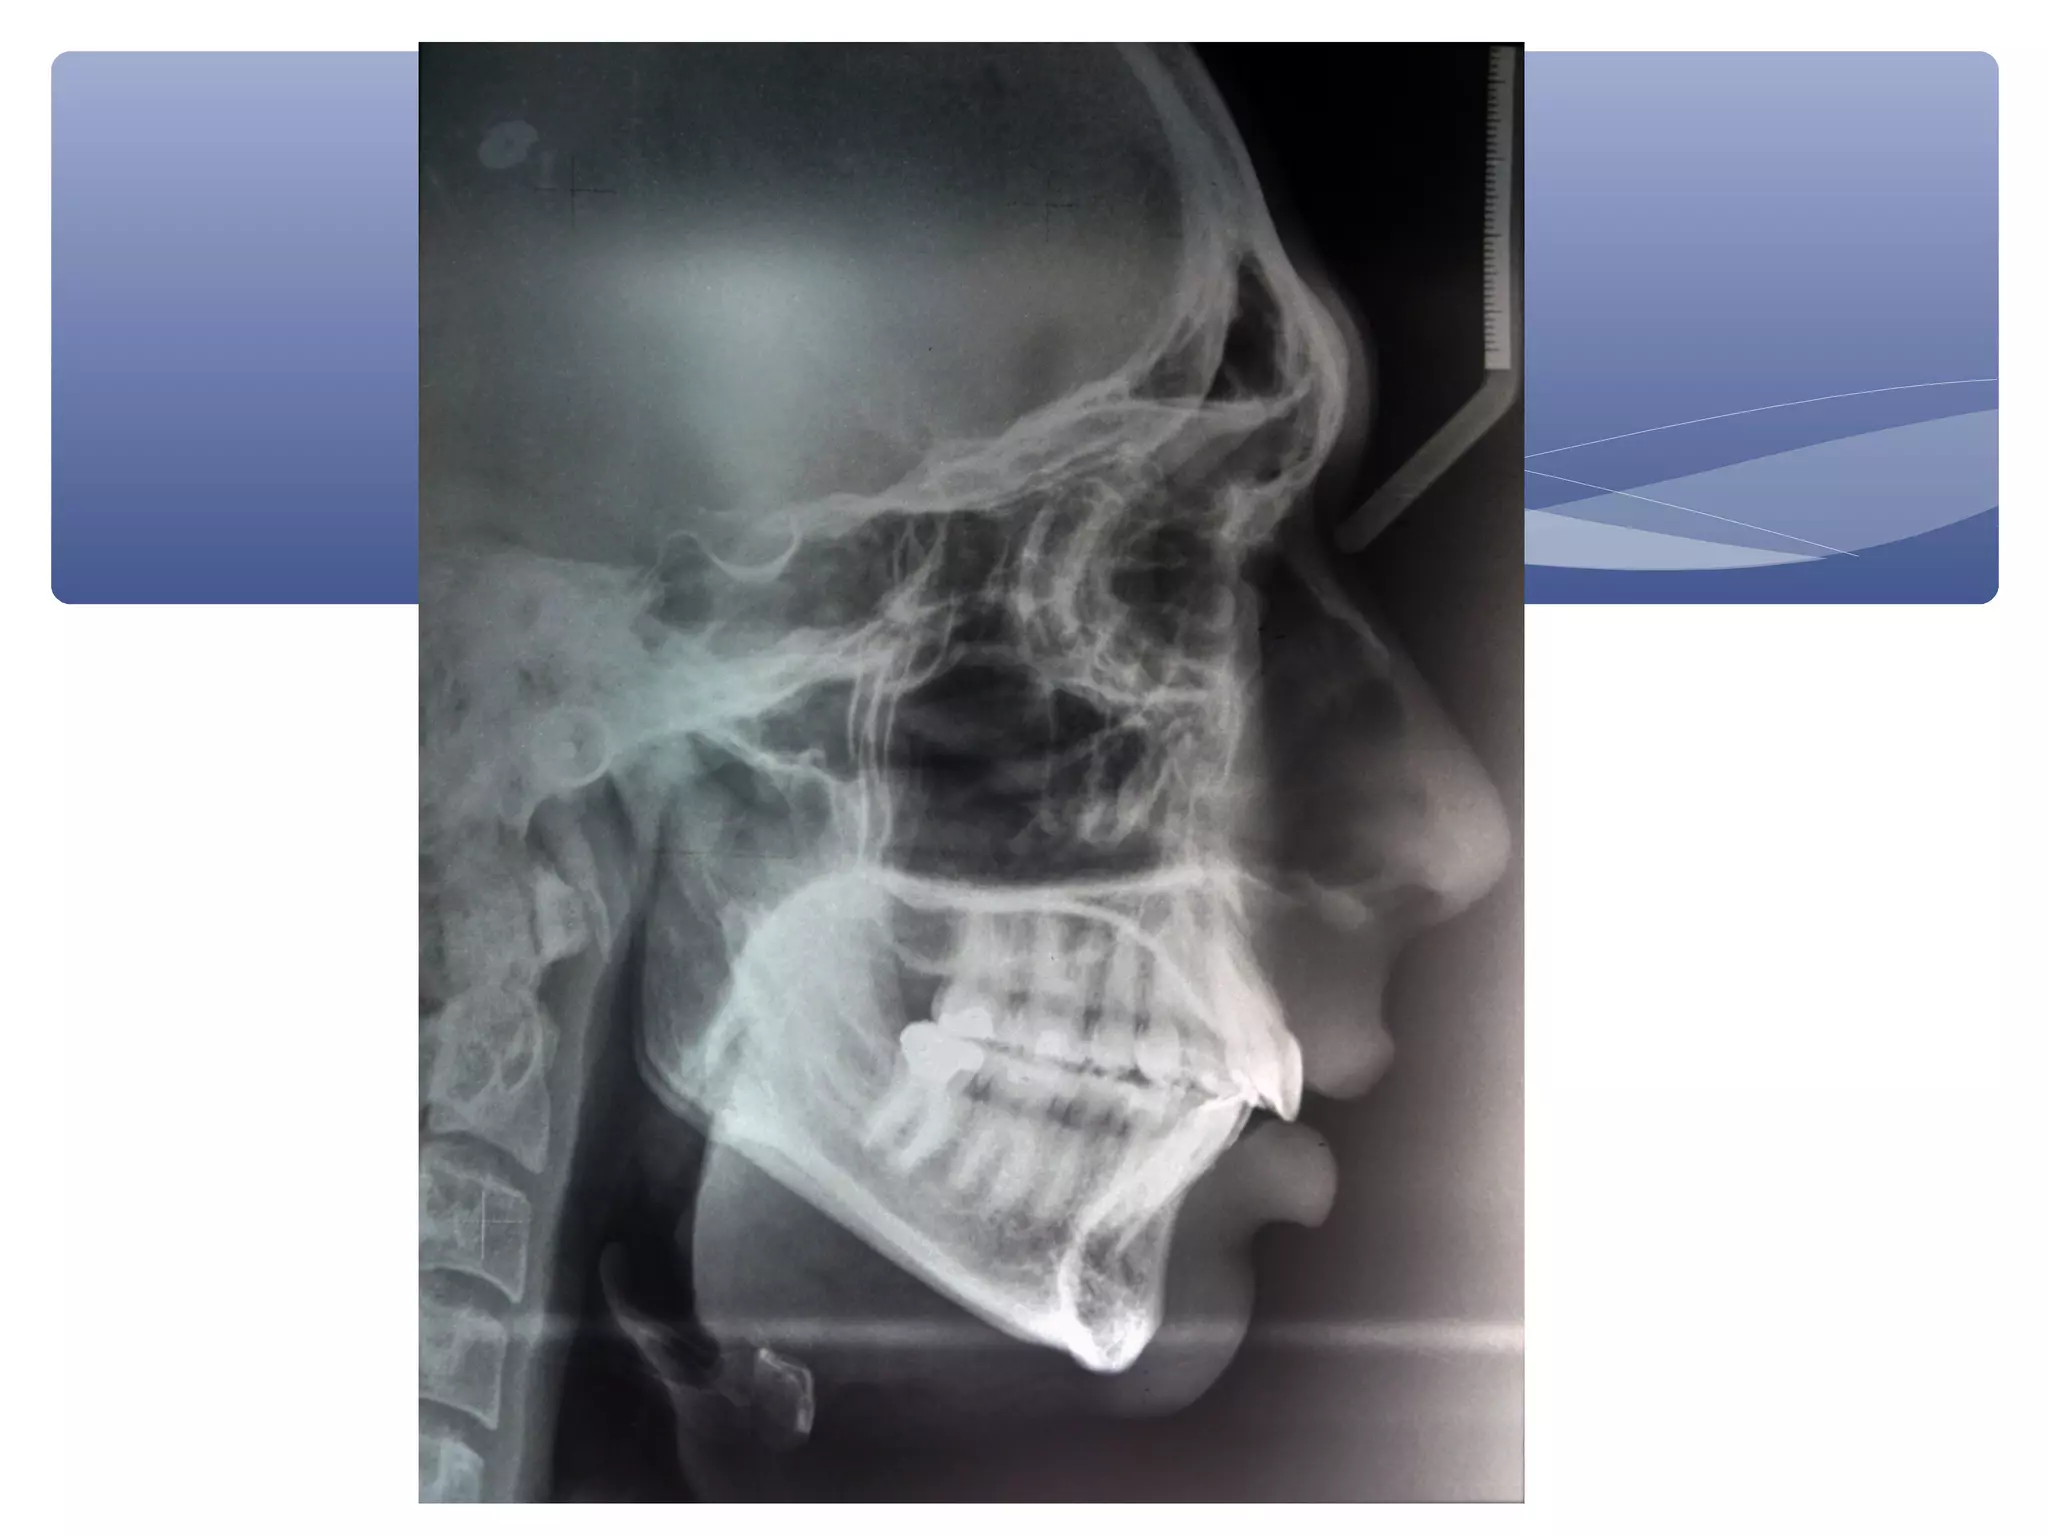

NORMAL

PATIENT VALUE

INFERENCE

DENTAL

Point A line

5 mm + 1 mm

13 mm

Proclined upper incisor

Point B line

2mm + 1mm

5 mm

Proclined lower incisor

Pogline

2 mm

8mm

Retruded chin

SKELETAL

Max base length

-

56

Mandibular base length

Anterior lower facial height

66

Posterior lower facial height

38

RATIO

1:1:1

1:1:0.9

Near balanced ratio

Anterior upper facial height

62

AUFH:ALFH

45:55

Angle of convexity

165° - 175°

169°

Sagittal angle

23° + 1°

29°

Convex angle

A:B:C:D

1.0:1.45

1:1.02

Unequal proportion

62:66

Increased AUFH

(mild skeletal

disturbances)